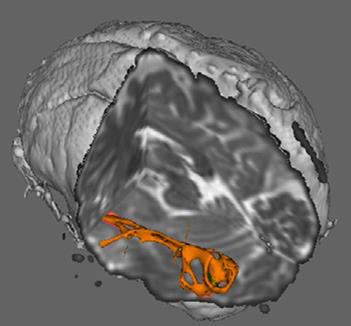

As part of a multidisciplinary team of Vanderbilt researchers she uses neuroimaging to compare children with dyslexia to typically developing readers, finding the brain’s white matter behaves differently in children with dyslexia.